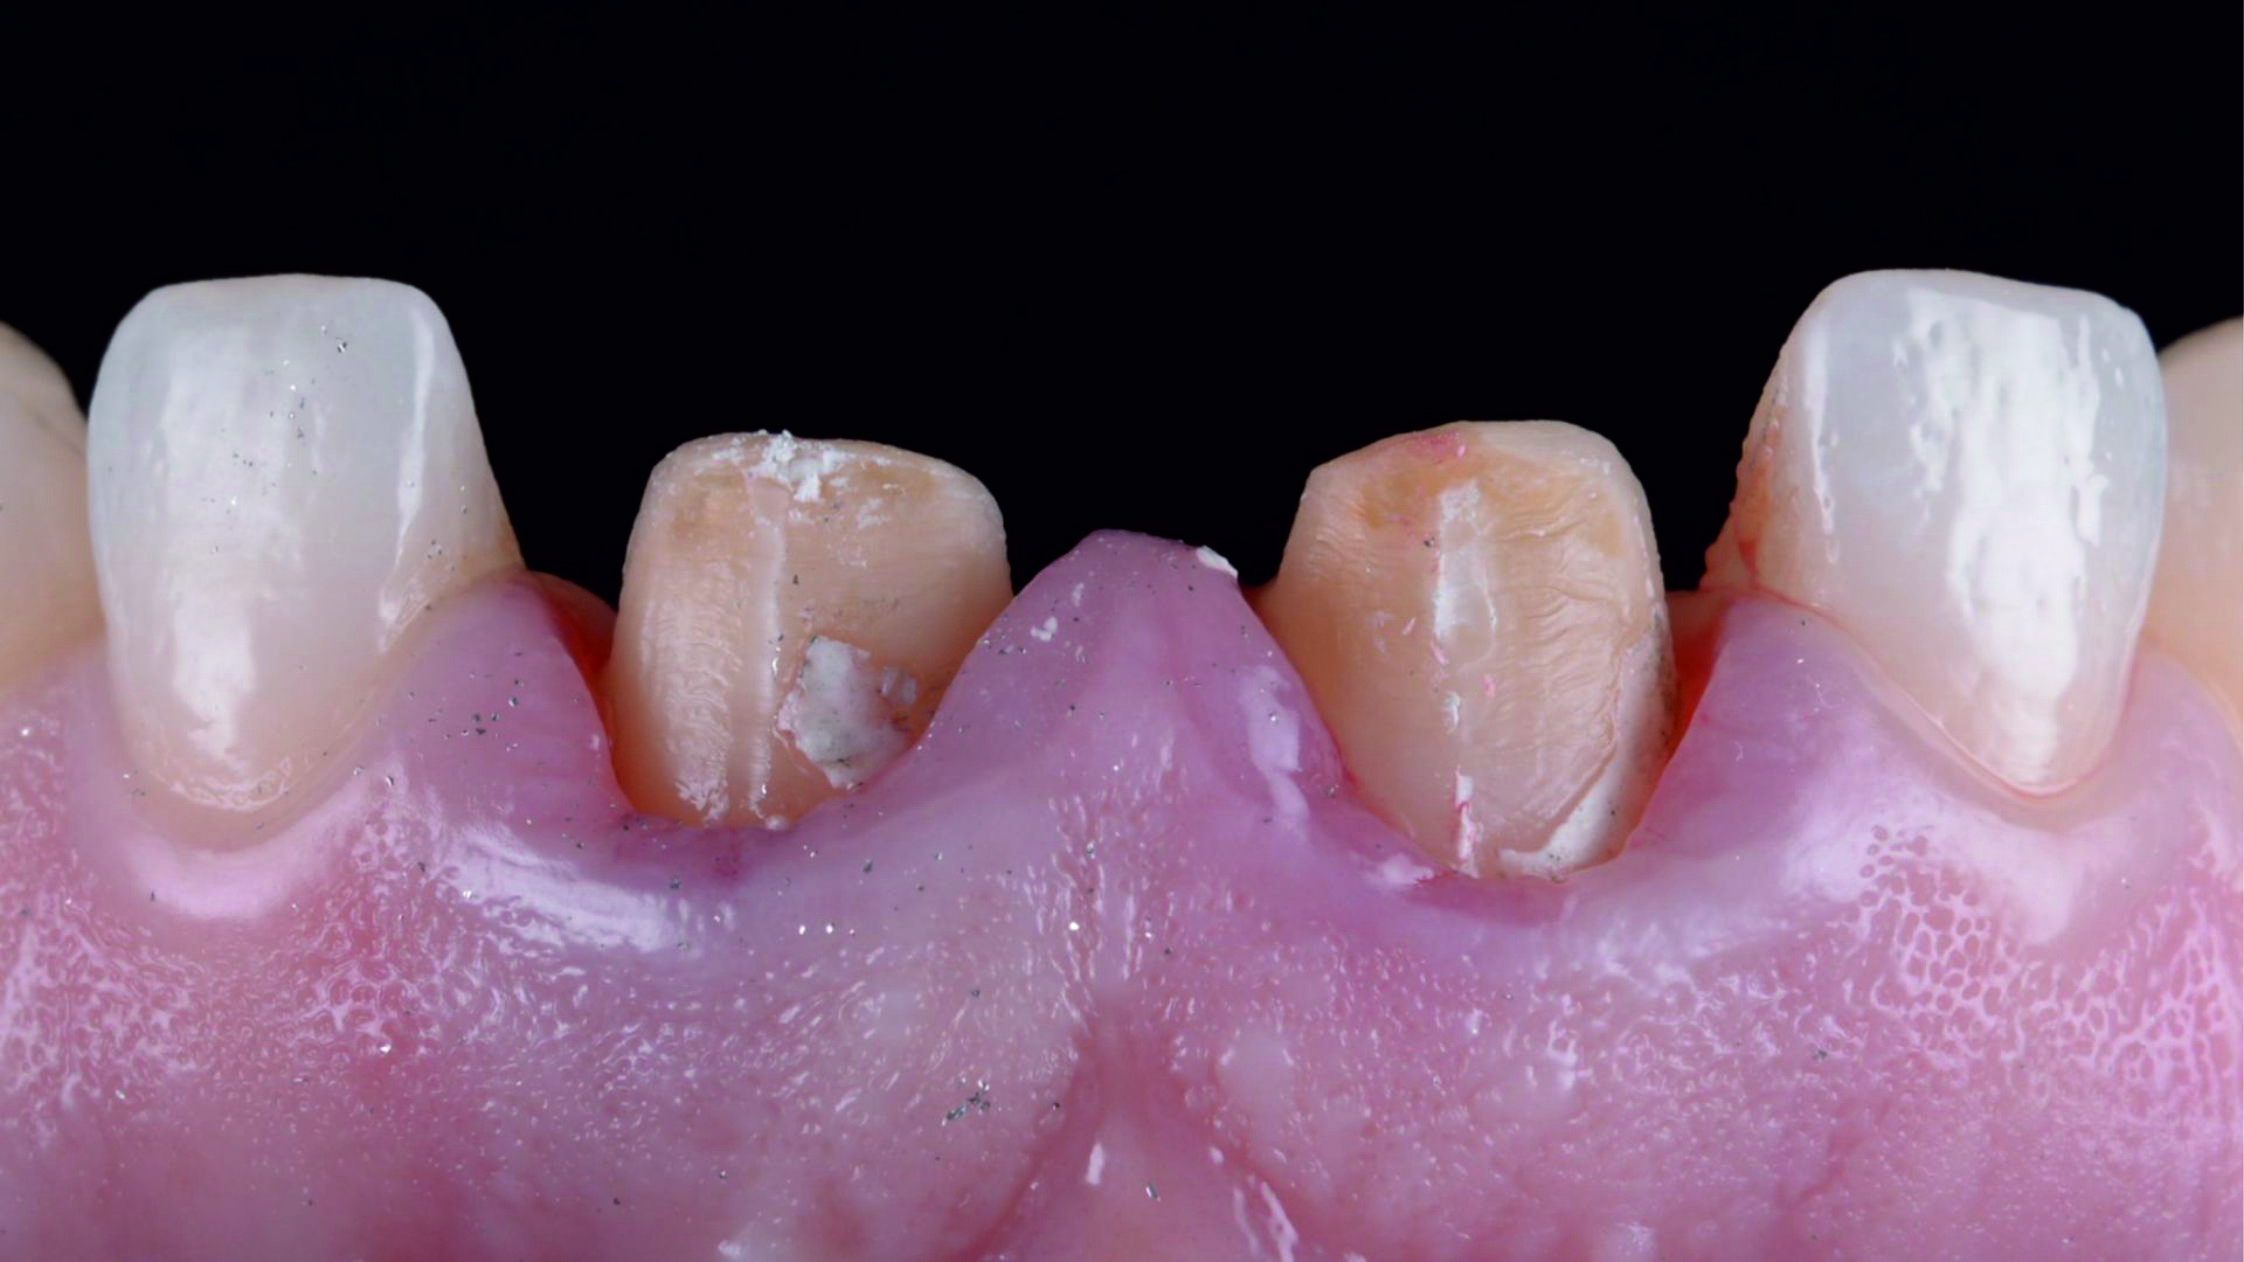

Фото 8. Після видалення штучних коронок видно, що кукси відпрепаровані з надлишком.Фото 9. Після усунення цементу, який залишився, та установки ретракційної нитки можна розглянути під’ясенну зону препарування, яка має різну глибину занурення, значно більше виражену в проксимальних ділянках кукс.

Фото 10. Проаналізувавши початкову ситуацію, можна сказати, що нам ще треба виконати низку складних маніпуляцій для препарування, встановлення тимчасових конструкцій, зняття відбитка та фіксації готових конструкцій.

Фото 11. Кукси реконструювали за допомогою композитного матеріалу і заново відпрепарували на тому ж рівні висоти шийки, на якому вони були відпрепаровані раніше.